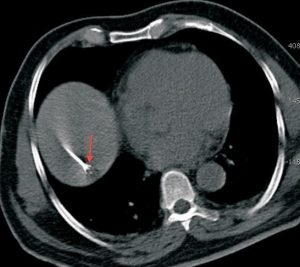

Recently we had an elderly gentleman with a solitary metastatic lesion (Fig. 1) measuring 1.2 cm in diameter in segment 7 of the liver, He had been operated earlier for carcinoma colon. We were able to safely introduce the RFA electrode into the lesion despite its deep location (Fig. 2), without puncturing the overlying pleura and lung, which were in the way. Since the lesion was close to the diaphragm, we had to take care to avoid puncturing the diaphragm. The lesion was ablated at 90 degrees for 7 ½ minutes and a good burn was achieved without any complications (Fig. 3).